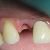

Paciente com ausência do incisivo lateral superior ,foi proposto a ele a rebilitação com implante e coroa metalocerâmica, reestabelecendo sua função mastigatoria e éstetica devolvendo assim a auto estima do paciente.

Fotos do caso